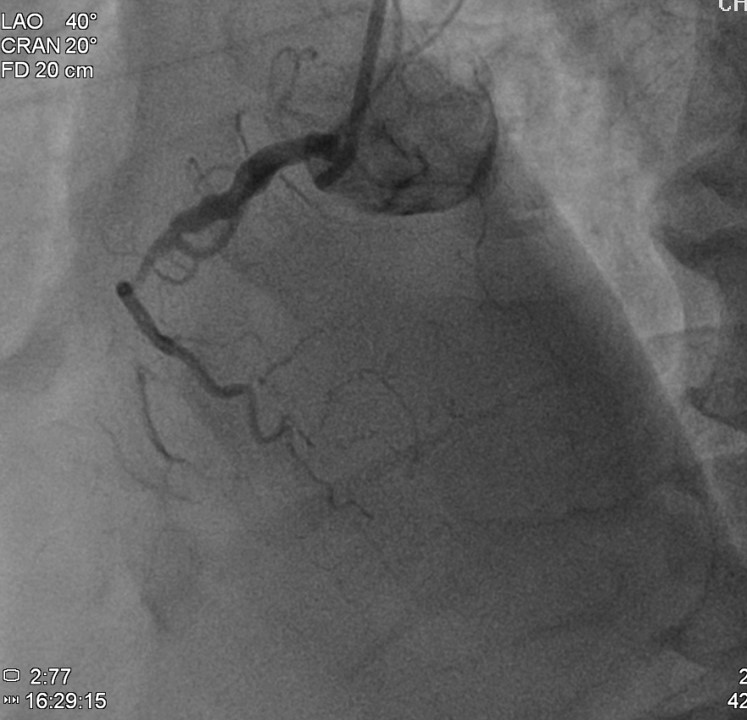

Coronary angiogram found 3-vessel disease with middle left anterior descending artery (LAD) total occlusion, and middle left circumflex (LCx) plus middle right coronary artery (RCA) chronic total occlusion (CTO).

The patient received primary percutaneous coronary intervention (PCI) with balloon angioplasty (POBA) and a drug-eluted stent (DES) for middle LAD. Three days later he underwent staged PCI for RCA. After wire externalization via rendezvous technique, the patient developed acute angina, diaphoresis, and hypotension. Angiogram found a de-novo LAD lesion just distal to the stent.

During the staged PCI, antegrade approach with escalating guidewires ended up in subintimal space; retrograde approach from the first LAD-septal branch failed because there was difficulty crossing the existing mid-LAD stent. Further attempts from the third septal branch successfully reached the distal cap of the CTO via proximal descending artery, finally entering the antegrade guide extension catheter by rendezvous technique. After wire externalization and POBA for RCA, the patient became agitated from acute angina, diaphoresis and hypotension. Angiogram of LAD found an acute de novo LAD lesion adjacent to the distal stent edge, leaving only TIMI-1 flow. We stopped the RCA procedure and wired LAD, performed POBA at the de novo LAD lesion and restored coronary blood flow. Then we continued PCI of RCA with POBA followed by the deployment of two DES. Final angiogram showed adequate stent expansion and TIMI-3 flow in RCA. The patient was discharged with no further complications. Follow-up echocardiogram three months later showed improved wall motion and ejection fraction, indicating good myocardial recovery.